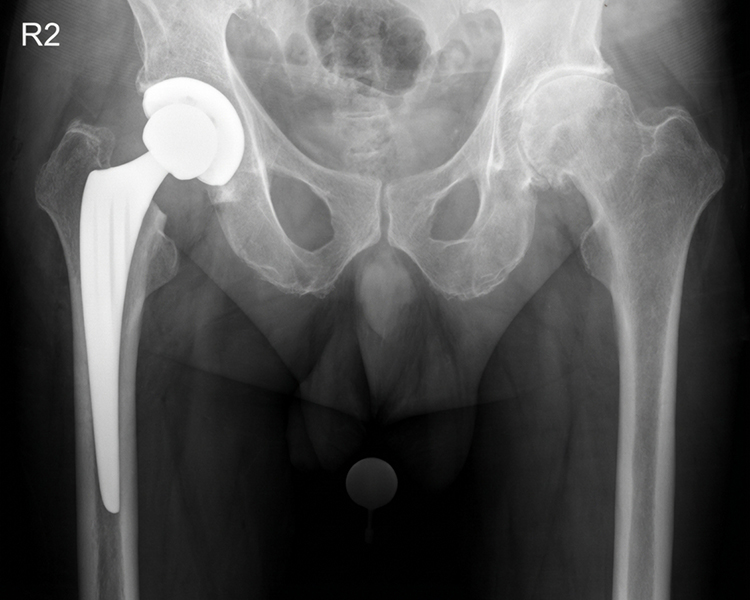

zementfreie Hüftendoprothesen

zementfreie SPCL Schaftprothese mit zementfreier Pfanne (Firma Link)

Hybrid-Hüftendoprothese (zementierter SP II-Schaft mit zementfreier Pfanne, Fa. Link)